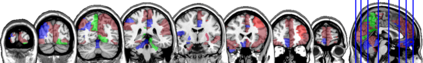

In this paper, we propose methods for functional predictor selection and the estimation of smooth functional coefficients simultaneously in a scalar-on-function regression problem under high-dimensional multivariate functional data setting. In particular, we develop two methods for functional group-sparse regression under a generic Hilbert space of infinite dimension. We show the convergence of algorithms and the consistency of the estimation and the selection (oracle property) under infinite-dimensional Hilbert spaces. Simulation studies show the effectiveness of the methods in both the selection and the estimation of functional coefficients. The applications to the functional magnetic resonance imaging (fMRI) reveal the regions of the human brain related to ADHD and IQ.